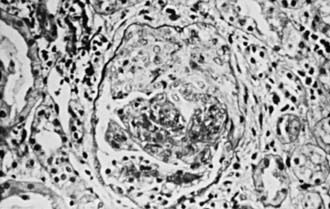

Figure 510-1 Light micrograph of a biopsy specimen from a child with Henoch-Schönlein purpura glomerulonephritis demonstrating a crescent overlying the glomerulus (×180).

“Rapidly progressive” describes the clinical course of several forms of glomerulonephritis (RPGN) whose unifying feature is the histopathologic finding of crescents in the majority of glomeruli (Fig. 510-1). Therefore the terms rapidly progressive glomerulonephritis (RPGN) and crescentic glomerulonephritis (CGN) are synonymous. The natural history of most forms of CGN is rapid and relentless progression to end-stage renal failure.

The hallmark of CGN is the histopathologic finding of crescents in glomeruli (see Fig. 510-1). Crescent formation, through proliferation of parietal epithelial cells in Bowman’s space, may be the final pathway of any severe inflammatory glomerular injury. Fibrin deposition and macrophage infiltration in the same areas suggest prominent involvement in the pathogenesis of the epithelial cell proliferation. Fibrous crescents, in which proliferative cellular crescents are replaced by collagen, are a late finding. The immunofluorescence findings, as well as the pattern of any deposits by electron microscopy (EM) can delineate the underlying glomerulopathy in CGN secondary to lupus, HSP nephritis, MPGN, postinfectious GN, IgA nephropathy or Goodpasture disease. Rare or absent findings by immunofluorescence and EM typify pauci-immune GN (Wegener disease and microscopic polyangiitis) and idiopathic crescentic GN.